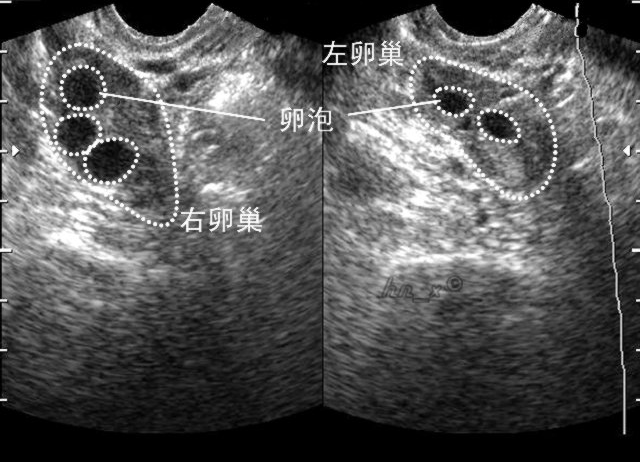

2. 超声监测排卵

超声监测是观察卵泡发育最直接、最可靠的方法之一。卵泡监测一般从月经的第3-5天开始。

超声连续监测可见在排卵前卵泡不断长大,当最大的卵泡消失时,提示发生排卵。